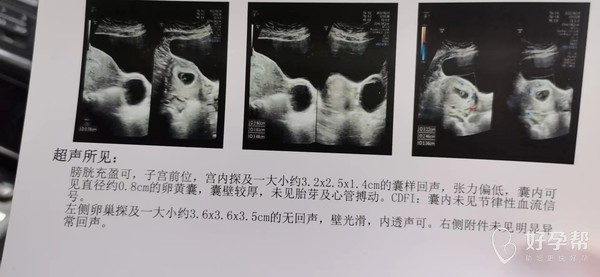

你好,这个彩超正常,应该没长切口附近,不然肯定会有描述的,放心吧,定期产检,祝好孕。